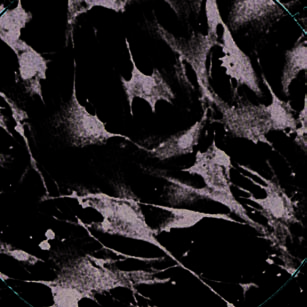

growth of other cells. When fibroblasts turn off, they

FIBROBLA

STS PHO